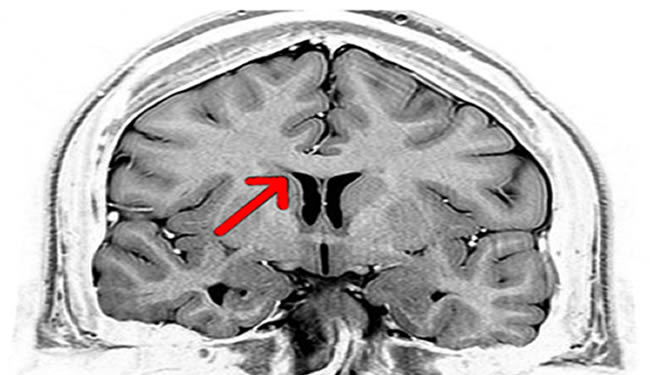

Şimdi prensesim güzelim, insan beyni kabaca sağ yarım küre, sol yarım küre ve ikisinin ortasında arkadan onlara bağlı olan cerebellum denen üç ana yapıdan oluşuyor. Cerebellum’u boşverelim, bu sağ ve sol yarım küreye odaklanalım. Bu iki yarım küre birbiriyle tamamen simetrik bir kere, birinde olan her alan her kıvrım, ötekisinde de var. Ama bu iki yarım küreye gelen bilgiler birbirine tamamen zıt. Vücudunun sağ tarafından gelen bütün sinyaller sol yarım küreye, sol tarafından gelen bütün sinyaller sağa gidiyor. Sağ gözünle gördüklerin, sağ bacağından gelen ağrılar hep sola, soldakiler de sağa. Neden böyle garip bir çaprazlama bilgi akışı var bana sorma, hiç bir fikrim yok.

Ama beyninin ve senin doğru düzgün işleyebilmen için tabii ki bu bilgilerin bir şekilde birleştirilmesi ve ona göre koordineli hareket edebilmen gerekiyor. Yoksa ne biliyim arada sağa çekersin arada sola falan Fransızlardan beter olursun. İki yarım küre arasında bilgi akışını sağlayan köprü corpus collosum denen beynin sağ ve sol yarım küresini birbirine bağlayan kalın bir kablolar ağı (ya da nöronların diliyle aksonlar yumağı). Corpus collosum üzerinden beyninin sağ ve sol yarım küreleri sürekli birbiriyle bilgi alışverişi yapıyor.

Gibi artık iki yarım küre birbiriyle ne konuşursa o tadda muhabetler iste. Benim bu yazıda bahsetmek istediğim ayrık beyin vakaları işte beynin iki yarım küresi arasındaki bu muhabbeti kesince ortaya çıkıyor. 1950’lerde epilepsi hastalarının tedavisi için corpus callosotomy adlı, kabaca cerrahi olarak corpus collusum boyunca bir kesit ile iki yarım küre arasındaki iletişimi kesmek. Temel mantık epilepsi nöbetleri beynin farklı noktalarında başlayıp bütün beyne yayılıyor. İki yarım küre arasındaki iletişimi kesersek, en azından beynin herhangi bir yarım küresinden başlayan bir epilepsi nöbeti, diğer yarım küreye sıçrayamaz (Dipnot corpus callosotomy hala epilepsi tedavisinde kullanılan bir yöntem, yalnız ayrık beyin vakalarından sonra tüm corpus collosumu kesmek yerine, belli bir kısmı kesiliyor artık).

Korpus Kollusum : Beynin her iki tarafında bulunan ilişkili asosiyon korteks bölgelerini birbirine bağlayan geniş akson demetidir. sayesinde bütün olarak görürüz, duyarız …